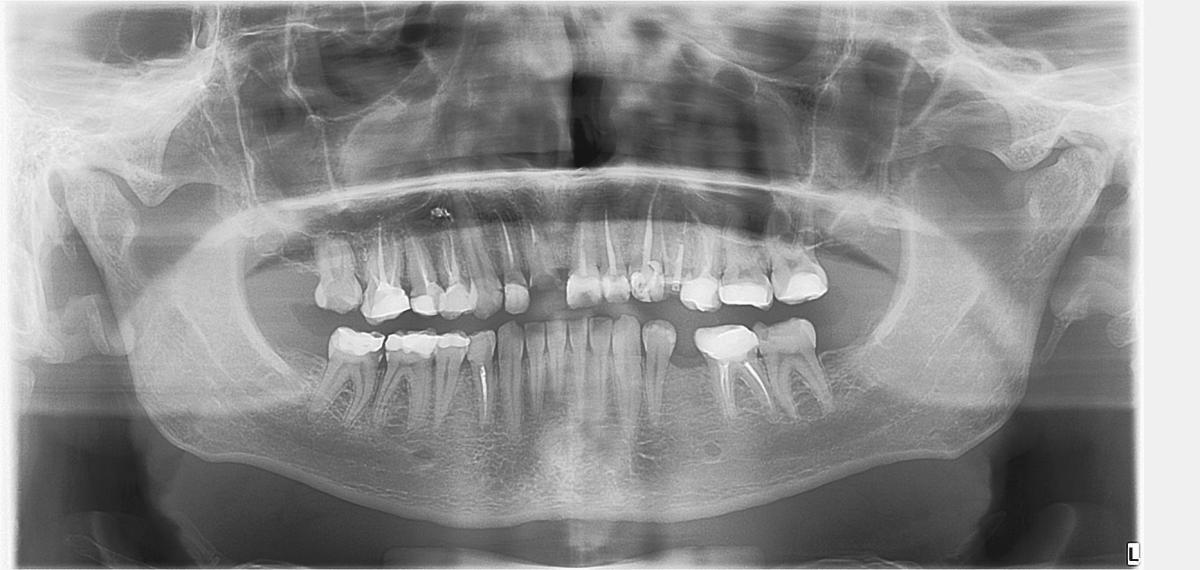

Здравствуйте, предстоит тотальное протезирование. Скажите, пожалуйста можно ли резец восстановить коронкой или только удаление?

И конень не пролечен, и коронковая часть зуба практически=0, зачем брать такие риски и вкладываться, не рассчитывая априори на длительный период использования, хотя бы 3-5 лет?

Согласна с предыдущим мнением доктора.Если бы разговор шёл об отдельно стоящий зубе и коронке на него,то можно было бы пробовать спасти.

А поскольку речь идёт о тотальном протезировании,то риск не нужен.Единственное,что посоветовала бы,после удаления заполнить лунку удалённого зуба аллографтом(костным имплантатом) для последующего сохранения костной структуры.

SGanem, Анна Адеева, спасибо вам. Скажите, пожалуйста, врачи говорят, что надо резцы с пломбами менять на коронки. Но, если смотреть на снимок выше, после удаления пломб своего зуба останется столько же примерно, сколько и там, где вы сказали уже не восстановить. Есть ли повышенная вероятность в данном случае, что после удаления пломб окажется, что там тоже уже можно только поставить импланты и удаление пломбы было зря ? Может быть есть любая другая полезная информация, которую можно понять по панорамному снимку ? Мне также собираются ставить винт, чтобы увеличивать место под имплант на нижней челюсти

AnonimQues, Ваша логика понятна,но при препарировании зубов под коронки,пломбы обрабатываются частично,а не удаляются полностью,а дальше уже врач при осмотре принимает решение,если стоит укрепить зубы штифтовыми культевыми вкладками или нет.